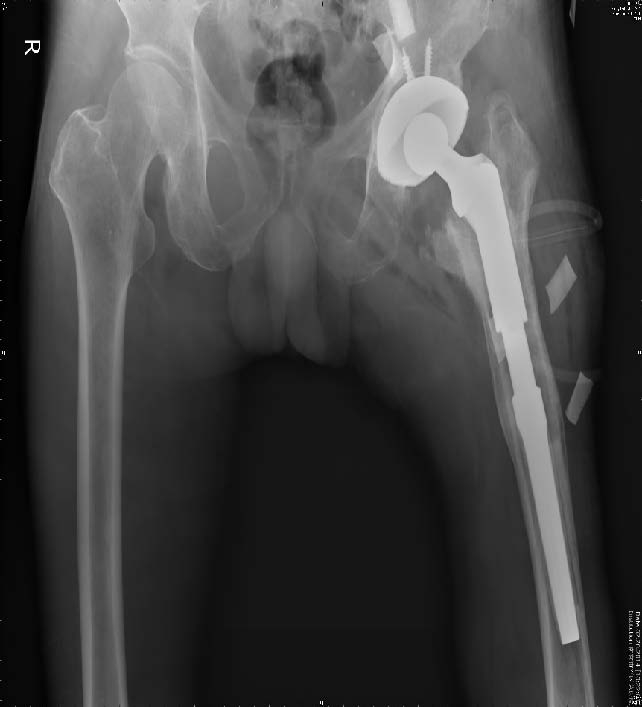

图2 同一患者,翻修术后第2 天双髋X 线片示远端固定长柄生物MP 假体位置良好

图3 同一患者,术后6 个月双髋X 线片示左侧MP 假体位置好、无松动